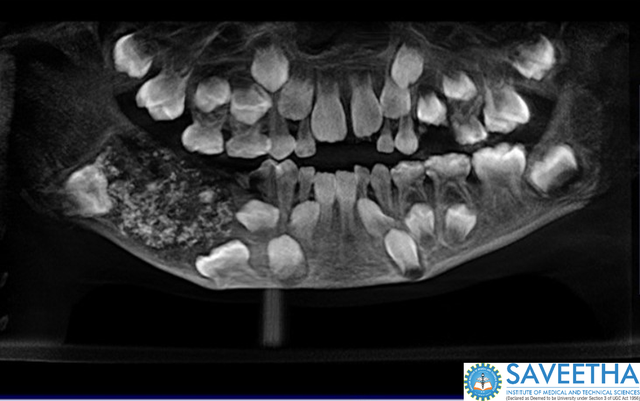

The boy was brought to the hospital with swelling in his lower right jaw, and he was found to be suffering from "compound composite ondontome," according to a press release from the hospital.

When he came back at age 7, his parents worried that he might have cancer in his jaw. The doctors decided to operate, and found what they described as a "bag like mass, which was removed in its entirety," according to the press release. The sack weighed almost half a pound. Inside were 526 tooth-like structures.

They ranged in size from 1mm to 15mm and resembled a tooth with a crown covered by enamel and a root-like structure. It was unlike anything the doctors had seen before. "This pandora box of miniature teeth is a jewel on our crown," doctors said.